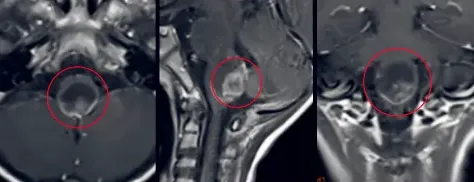

综合治疗失效后的选择

2023年,7岁的轩轩因头痛、呕吐、走路不稳等症状就诊,MRI检查发现第四脑室底部存在占位性病变。在当地医院接受开颅肿瘤切除术,术后病理诊断为"间变型室管膜瘤WHO III级"。术后影像学检查证实肿瘤存在残留。为控制残留病灶,轩轩接受了为期一年的质子放疗。然而治疗结束后,症状并未缓解,反而出现明显的吞咽功能障碍。复查MRI显示,肿瘤不仅复发,且已浸润至脑干右侧深部区域,脑干受压变形。考虑到肿瘤位置特殊,二次手术可能导致呼吸衰竭或高位截瘫,多数医生建议继续保守观察。不愿放弃的轩轩家人最终通过INC联系到德国巴特朗菲教授进行远程咨询。巴教授详细了解情况后给出明确判断:肿瘤生长迅速,存在明确的显微外科手术指征,首要任务是移除肿瘤,之后可考虑辅助放疗。这一决策建立在儿童室管膜瘤治疗的核心逻辑之上:手术切除程度是影响预后的最重要因素,二次手术具有可接受的安全性与有效性。不久后,巴特朗菲教授抵达中国,轩轩成为巴教授中国行的小患者之一。巴教授采用枕下后正中入路行第四脑室肿瘤显微切除术,全程使用神经电生理监测。术后影像学证实肿瘤实现肉眼全切。术后第一天,轩轩清醒,肢体功能较术前有所恢复;术后第十五天,孩子顺利出院;术后第五个月,孩子的吞咽功能和运动功能显著改善,精神状态良好,已回归校园,并按照巴教授建议继续接受辅助质子治疗。